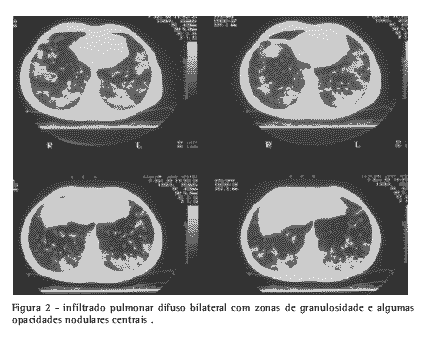

Estudo imagético: tomografia computadorizada de tórax com infiltrado pulmonar difuso bilateral, com zonas de granulosidade e algumas opacidades nodulares centrais. Não havia evidência de adenomegalias no mediastino (Figura 2).

Avaliação micológica: soromicologia com imunodifusão para H. capsulatum negativa; histopatologia: segmento de língula (obtido por biópsia pulmonar) corado por hematoxilina e eosina com granuloma tuberculóide com necrose caseosa e fibrose em parênquima pulmonar; técnica de Gomori-Grocott com metenamina argêntica com numerosos elementos leveduriformes pequenos ovóides e esferóides, unibrotantes, sugestivos de H.capsulatum; o exame de cultivo foi negativo.

Este padrão radiológico incomum é sugestivo de grande inóculo em zona não endêmica, causando grande reação inflamatória(1). O cultivo é positivo somente em 15% nas formas auto-limitadas (4).